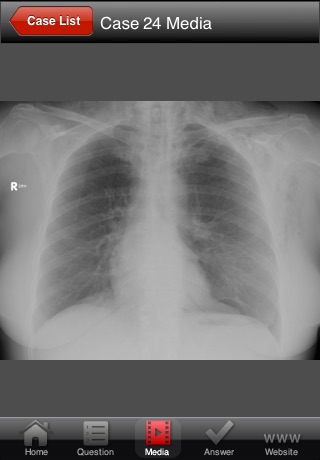

Data interpretation is essential to all clinicians who care for critically ill patients. The ability to recognize common patterns of disease or investigation results is fundamental to establishing the correct diagnosis. This app will be valuable to all critical care clinicians by providing them with instant "experience", so that when they come across something in practice, they will be able to recognize it.